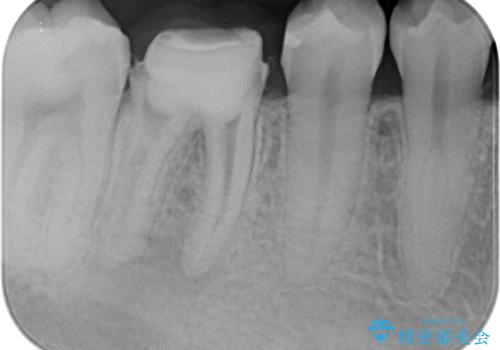

治療後は症状も改善し、半年後の経過も良好です。